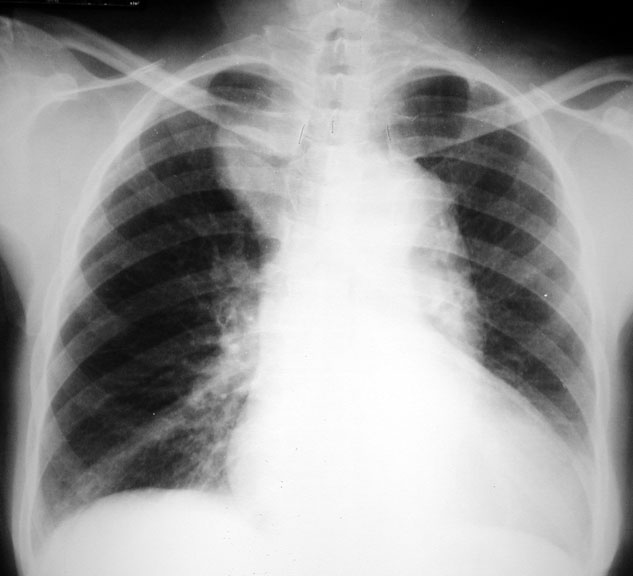

Dissecting Aneurysm

• Mediastinal widening

• Left diaphragm indistinct

• Intimal calcification displaced inwards

• Angiogram: Double lumen